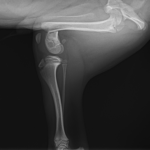

幼犬の大腿骨遠位の骨折です。幼犬は治癒能力が高く、仮骨の形成が早期に起こります。しかしながらこの時期は骨質が大変柔らかく固定には注意が必要です。本来であれば成長板をまたぐ固定は避けたいところですが、やむを得ず軽量のTitanium Locking Plateを用いて固定術を行いました。早期に抜釘することになります。